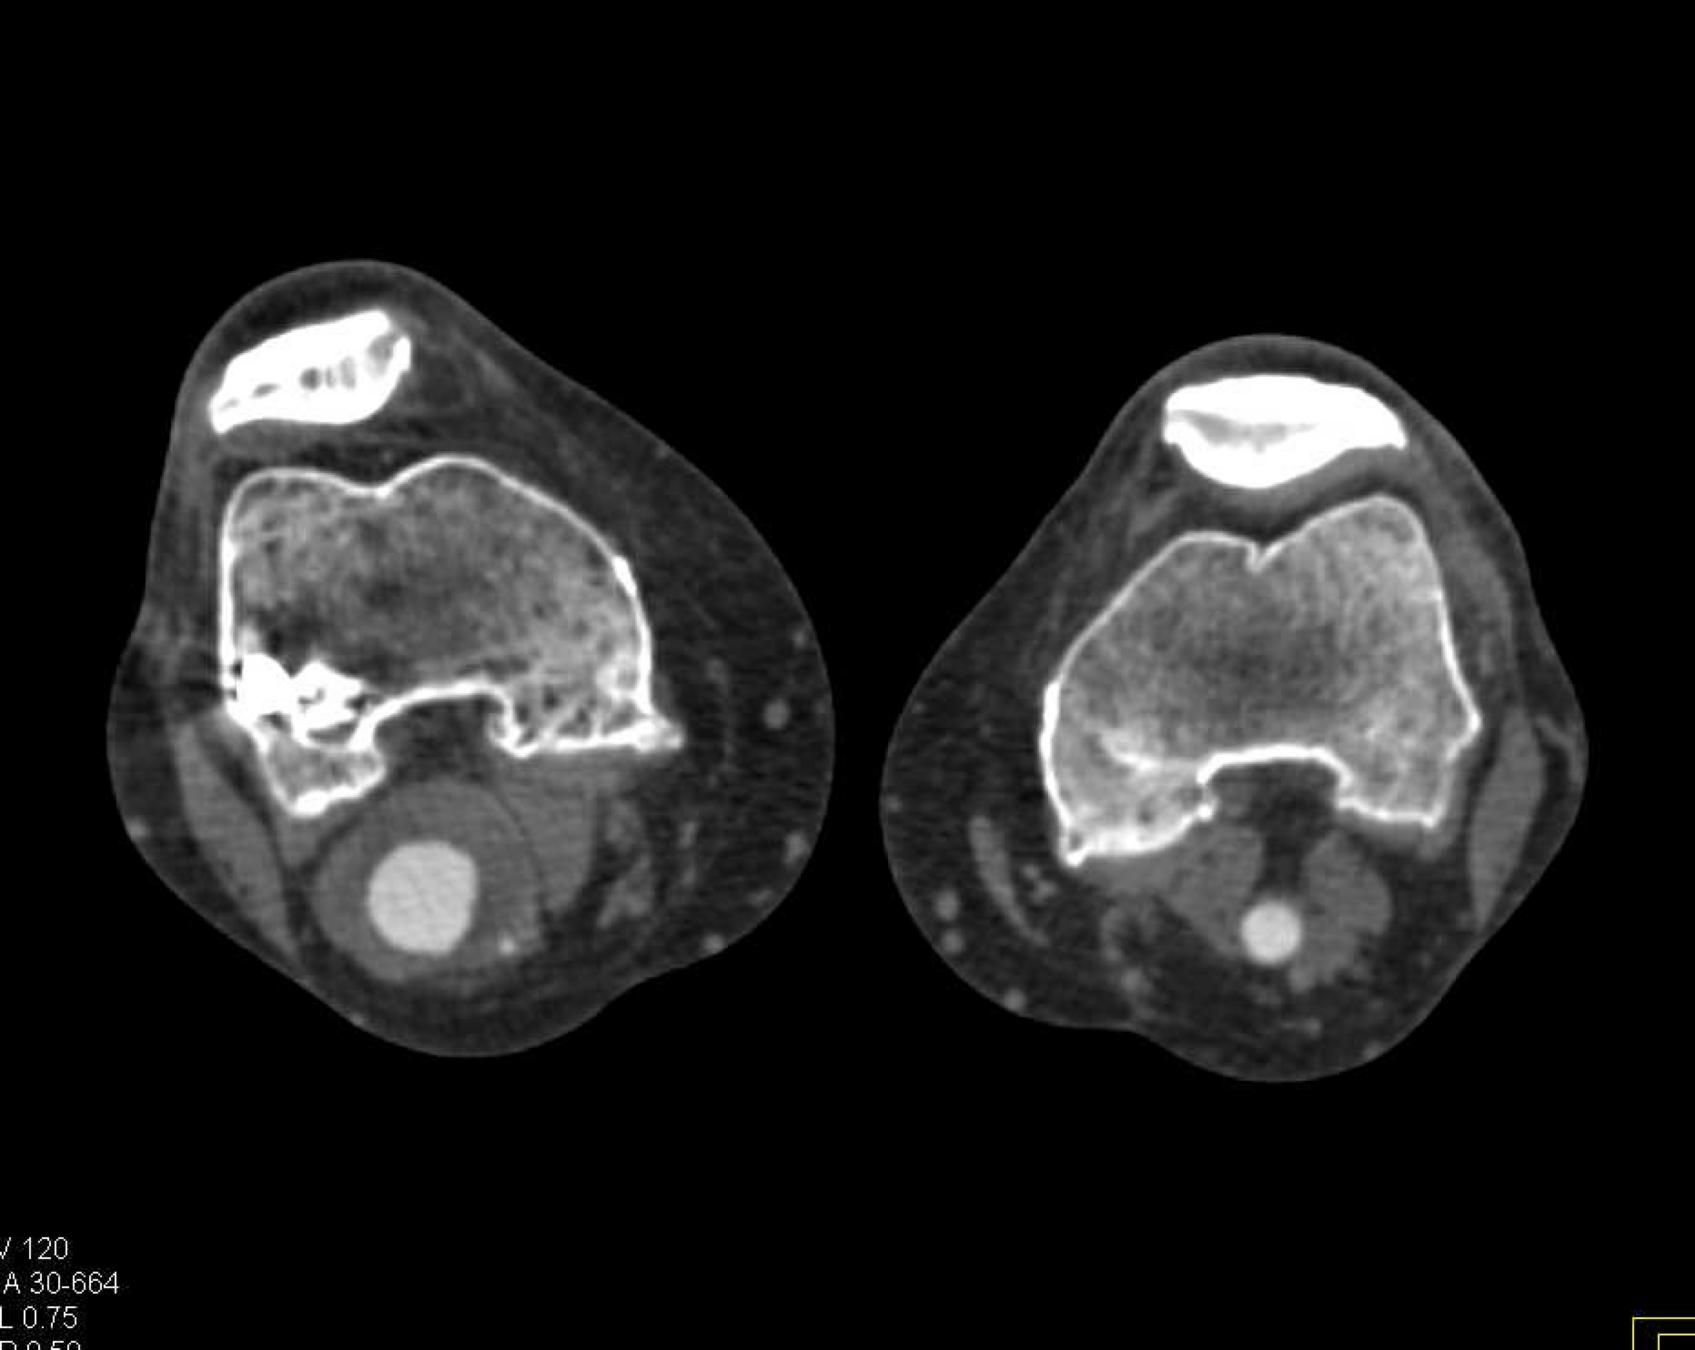

Here is the original image of a knee CT scan with a popliteal artery aneurysm (PAA) before pre-processing (courtesy of CTisus):

Original Image